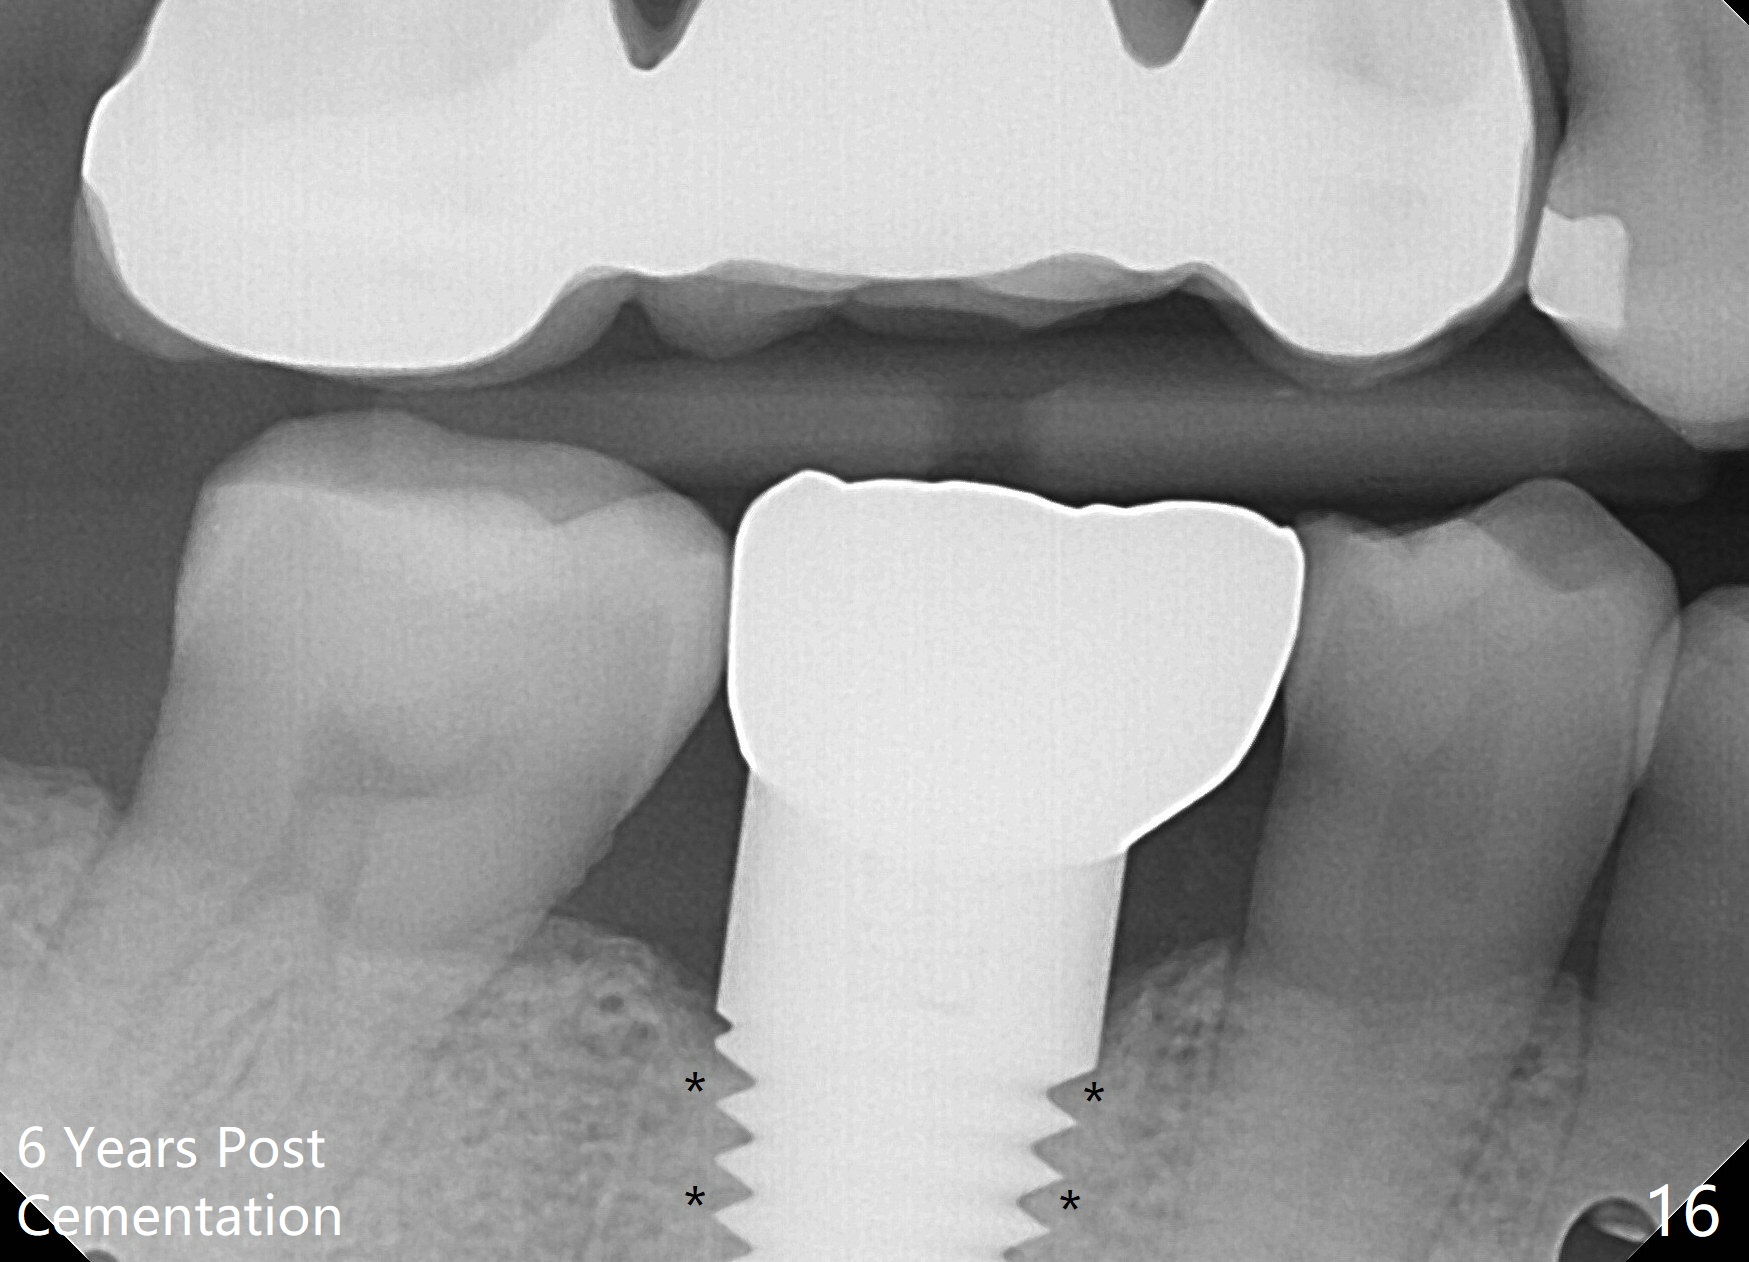

When a large implant is placed in a molar socket, one dimension of the remaining socket is small (buccolingual for lower, mesiodistal for upper). It is apparent that the mandibular buccal and lingual gingiva is relatively loose for the most time, the mesial and distal socket could be closed by suturing and perio dressing. The maxillary palatal gingiva is particularly thick and tough to be approximated. It appears necessary to develop a technique using an immediate provisional to close the socket or place an abutment. Cortex-like bone seems to have grown into the mesial thread spaces 3 years post cementation (Fig.13 <). The 7x17 mm implant was placed buccal (Fig.14 B). The slowly resorbed buccal plate seems to darken the buccal gingiva (Fig.15 B). The bone next to the implant is dense 6 years post cementation (Fig.16 *). The implant at 19 should be smaller and placed lingual.